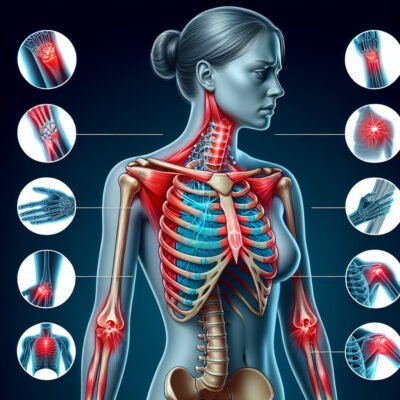

Синдром грудного виходу

Що таке синдром грудного виходу?

В англомовній медицині це називається Thoracic Outlet Syndrome (TOS). Чули? Безліч людей мають цю штуку, навіть не знаючи назви. Усе через компресію нервів і судин між ключицею й першими ребрами. Простіше кажучи, щось тисне там, де не повинно.

Симптоми

Симптоми можуть бути найнесподіваніші! Ось кілька:

- Біль у плечах або шиї

- Оніміння в пальцях рук

- Слабкість у м’язах

- Відчуття тяжкості в руці